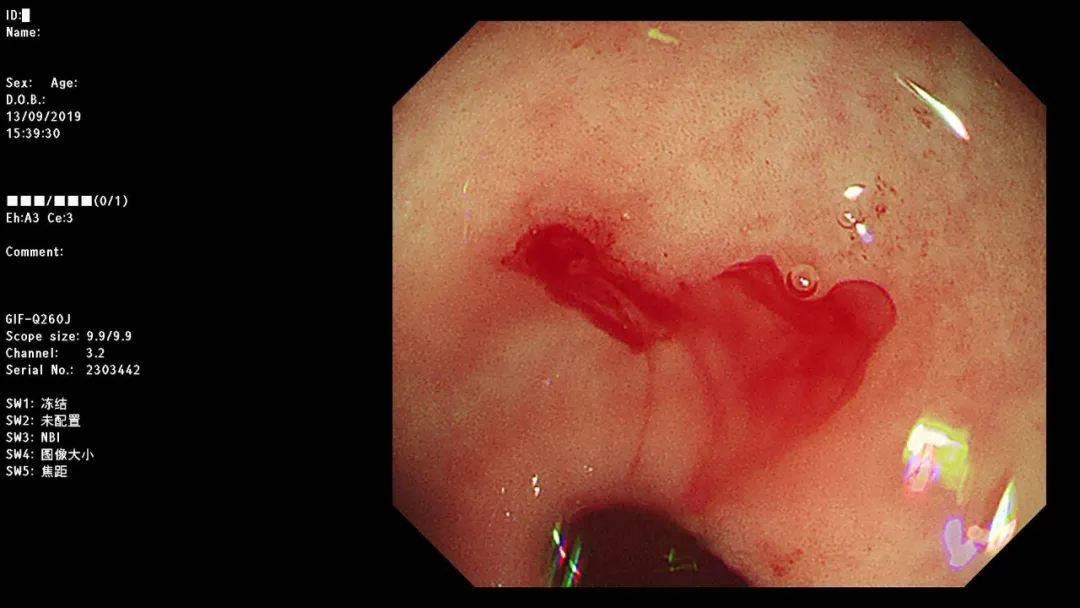

病例一:男,停止排气排便4天,CT提示乙状结肠占位,至急诊外科就诊。

急诊肠镜示:距肛门20cm新生物,占据肠腔全周,放入肠道支架通过狭窄段,粪水流出,检查诊断:乙状结肠癌并梗阻急诊肠道支架置入术。